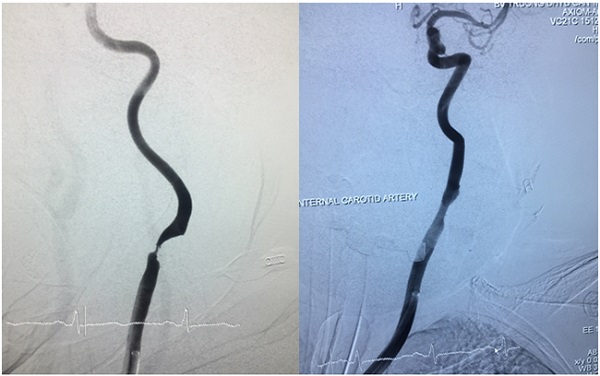

Trường hợp 2:

Bệnh nhân nữ, 68 tuổi, hẹp động mạch cảnh trong trái. Triệu chứng chóng mặt, yếu 1/2 phải, nói đớ, nhầm lẫn, có nhiều đợt mất ý thức thoáng qua.

Hình 2a: trước can thiệp                   Hình 2b: sau can thiệp

Sau can thiệp bệnh nhân cải thiện triệu chứng, tỉnh táo, không chóng mặt, cải thiện sức cơ, đi lại bình thường.